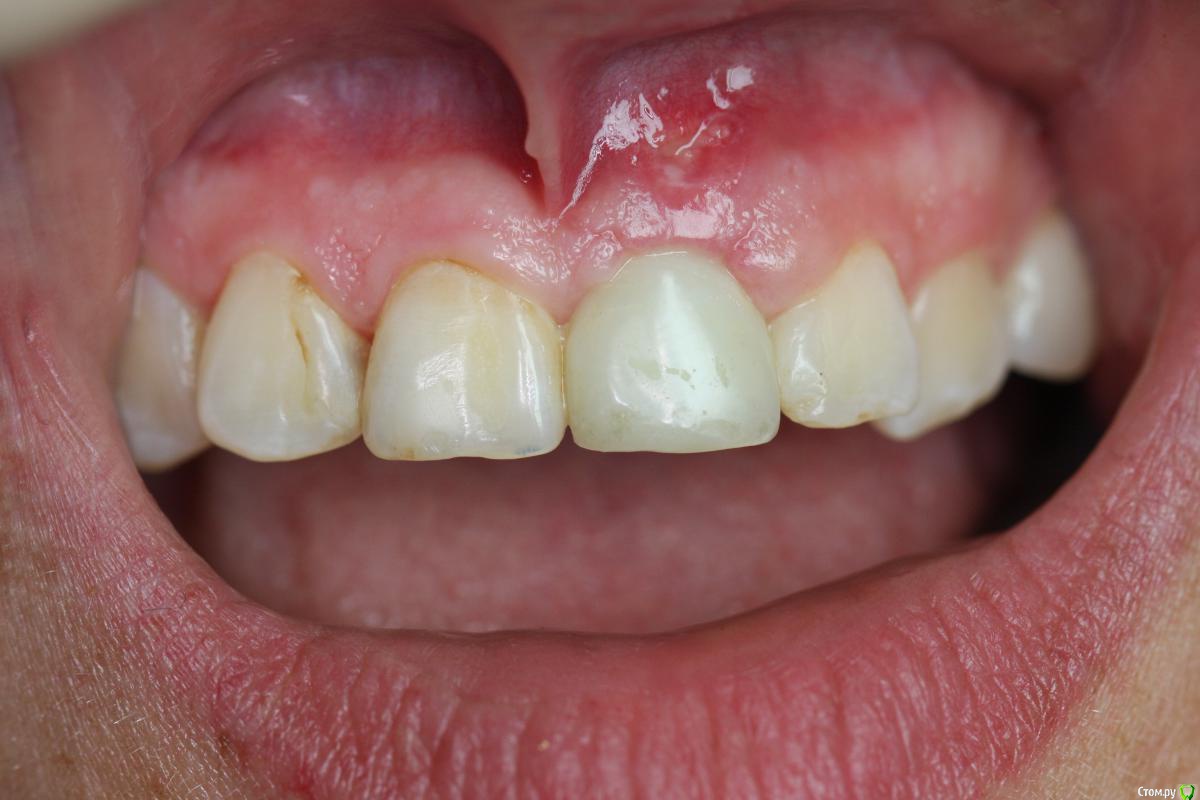

Zorrro Опубликовано 28 февраля, 2016 Поделиться Опубликовано 28 февраля, 2016 Пациента прислали на консультацию с кт. Огромная квк,ожидаемая трещина,локально гиперемия,подвижность коронки.Назначили аб терапию и записались на операцию через 2 дня.К сожалению нет фотодокументации с первой консультацией.Альтернативой немедленной нагрузки с костной и мягкотканной пластикой,были отсроченные костные блоки,с двухэтапным протоколом имплантации и тд и тп.С вероятным коллапсом мягких тканей,турбомобилизацией и прочими неприятными сопутствующими манипуляциями растянутыми по времени,а самое главное без ясного и прогнозируемого результата…короче решили рискнуть. Ссылка на комментарий

doca Опубликовано 28 февраля, 2016 Поделиться Опубликовано 28 февраля, 2016 Пациента прислали на консультацию с кт. image.jpegimage.jpegОгромная квк,ожидаемая трещина,локально гиперемия,подвижность коронки.Назначили аб терапию и записались на операцию через 2 дня.К сожалению нет фотодокументации с первой консультацией.Альтернативой немедленной нагрузки с костной и мягкотканной пластикой,были отсроченные костные блоки,с двухэтапным протоколом имплантации и тд и тп.С вероятным коллапсом мягких тканей,турбомобилизацией и прочими неприятными сопутствующими манипуляциями растянутыми по времени,а самое главное без ясного и прогнозируемого результата…короче решили рискнуть.И? 2 Ссылка на комментарий

Zorrro Опубликовано 29 февраля, 2016 Автор Поделиться Опубликовано 29 февраля, 2016 (изменено) Через два дня пациент меня неприятно удивил.И ,безусловно,правильно было бы отменить операцию и ограничиться удалением,но… Вот такой был сюрприз под носом с нечищенными зубами.Обговорив риски,перекрестившись начали.Во время операции фото не делал.Слизистая в проекции 21 была сильно истончена острым гнойным процессом,буквально светилась.в итоге после эвакуации гноя промыл фурацилином,установил анкилос А11,подсыпал остеопласт вестибулярно и укрыл это всё сст из бугра в качестве мембраны.ещё один сст пошёл навременный абатмент в виде "шашлыка".Через 10 дней Через 4 месяцас рекомендацией замены пломбы на 12 у своего доктора мы ипопрощались.пациентка осталась глубоко удовлетворённой,а это главное. Изменено 29 февраля, 2016 пользователем Zorrro 4 Ссылка на комментарий